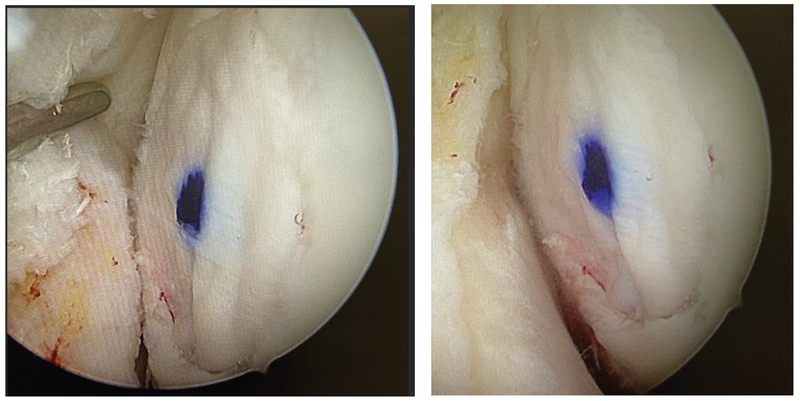

Matrix-augmented bone marrow stimulation (M-BMS)

The initial “treatment gap” for defect sizes between Mfx and M-ACT has been closed by now with the use of M-BMS scaffolds. Various biomaterials are available (Fig. 18, 19) [17].

The AMIC procedure has been used in our hospital for many years. In general, a diagnostic arthroscopy is performed first with treatment of the comorbidities (meniscus, arthrolysis, etc.). The indication is verified and documented. Then the osteotomy is performed. For the cartilage treatment the knee joint has previously been subjected to a short arthrotomy as a standard treatment. By now, arthroscopy instruments are available for some biomaterials. During preparation, the defect is stabilized at the margins or punched by arthroscopy and the base of the defect is debrided in stages and the subchondral layer is cleaned up. At this point, inferior subchondral bone can still be additively augmented with autologous spongiosa. During an osteotomy the spongiosa specimen can be harvested without problems from the osteotomy gap. After preparing the base of the defect, the size of the defect is measured via a foil template, transferred to the membrane and cut to size. In case of purely chondral defects, the subchondral holes are now drilled (Mfx or micro-drilling). The membrane is then inserted to the defect with the rough side and fixed either with fibrin glue or circular with fine (6-0) PDS sutures. (Fig. 21, 22).

In the arthroscopy procedure the defect is cut out via a hollow punch, the microdrilling is performed with K-wires via an arthroscopy sleeve guide and the membrane is glued in via the trocar (Fig 23 a−c and 24). Finally, the joint is moved through its entire range and the stability of the scaffold is verified.